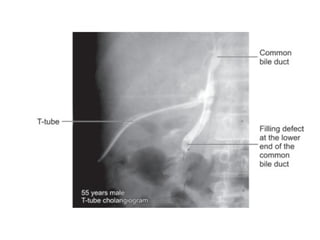

 T-tube cholangiogram in 10-14 days.

Mechanical flushing

 If the retained stone is small (< 1cm).

 Bile duct is irrigated with a heparinized

saline (250 mL of normal saline mixed

with 25,000 IU of heparin) by passing

the fluid through the T-tube tract for

consecutive 5 days.

 An injection of hyoscine may relax the

ampulla of vater and may facilitate the

expulsion of small stones.

Burhene technique

 Patient is discharged home with the T-

„

tube in situ, and a waiting period of 4–6

weeks allows the T-tube tract to get

matured. „ „

 A Dormia basket catheter is introduced

through the T-tube tract into the bile

duct and the stones may be removed. „